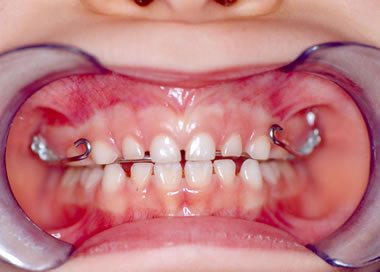

I° Caso- La piccola S.T. di anni 4 è giunta alla nostra osservazione per una visita ortodontica mandata dal suo pediatra di famiglia. All'anamnesi risultava che la bambina respirava prevalentemente con la bocca e durante la notte russava e andava i apnea. All'esame clinico ortodontico la bambina presentava un morso inverso anteriore con palato ogivale (Figura 1).E' stato richiesto quindi un monitoraggio cardio-respiratorio che è stato eseguito con un poly-mesam 8 canali portatile. Tale esame ha evidenziato un RDI =13 associato a forte russamento (Figura 2). Sulla radiografia del cranio in proiezione latero-laterale è stata eseguita l'analisi cefalometrica che ha messo in evidenza una I classe scheletrica con tendenza alla III in soggetto ipodivergente. In considerazione del morso inverso e del palato ogivale, si è deciso di applicare un espansore rapido palatale con ganci per maschera di Del aire (Figura 3). Ottenuta l'apertura della sutura palatina è stata applicata la Maschera facciale di Delaire per la trazione postero-anteriore del mascellare superiore. Dopo 2 mesi dall'inizio della terapia è stato eseguito un monitoraggio cardio-respiratorio di controllo che ha messo in evidenza un RDI= 5 con riduzione del russamento rumoroso (Figura 4). Dopo 6 mesi, ottenuta la correzione del morso inverso e del palato ogivale, una volta rimosso l'espansore rapido e la maschera facciale, è stato applicato un apparecchio funzionale di III classe come mantenimento. La correzione della malocclusione ha coinciso con il miglioramento dei sintomi respiratori come anche riferito dalla madre.